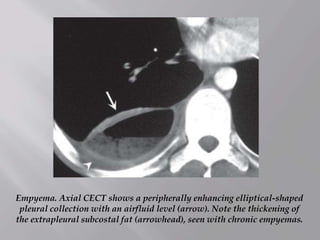

Empyema. Axial CECT shows a peripherally enhancing elliptical-shaped

pleural collection with an airfluid level (arrow). Note the thickening of

the extrapleural subcostal fat (arrowhead), seen with chronic empyemas.